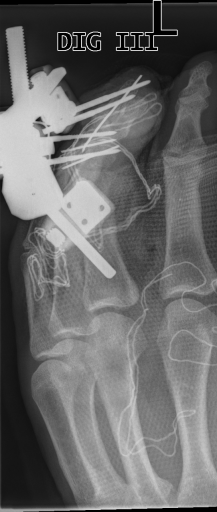

The Image Retrieval in Medical Applications (IRMA222http://irma-project.org/) database is a collection of 14,410 x-ray images that have been randomly collected from daily routine work at the Department of Diagnostic Radiology of the RWTH Aachen University333http://www.rad.rwth-aachen.de/. The downscaled images were collected from different ages, genders, view positions, and pathologies [3].

Figure 3 shows some samples images from IRMA dates along with their corresponding IRMA codes.